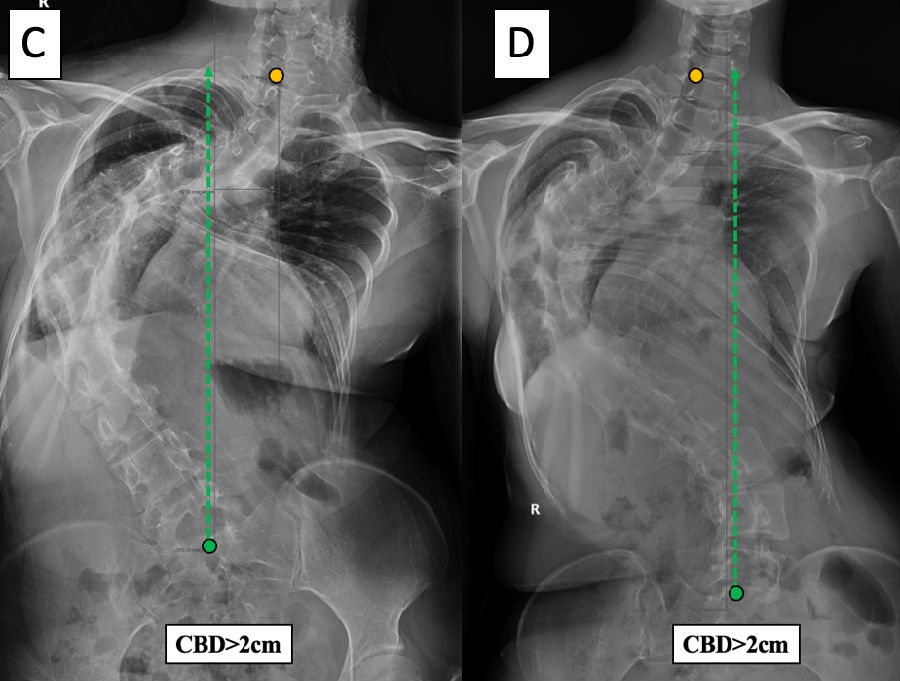

基于以上临床观察,我们提出了脊柱侧凸顶椎位置分布的冠状面平衡修正[7]。首先,根据CBD是否大于2cm,将患者分为冠状面平衡(coronal balanced, CB)和冠状面失平衡(coronal imbalanced, CIB)。然后,根据患者各个弯曲顶椎/椎间隙中心的分布特点,赋予顶椎位置分布修正(-/+),若果各顶椎中心分布在CSVL两侧,则为修正(-),若各顶椎中心分布在CSVL同侧,则为修正(+)(图7)。

图7. 基于CBD和顶椎分布修正的冠状面平衡分型